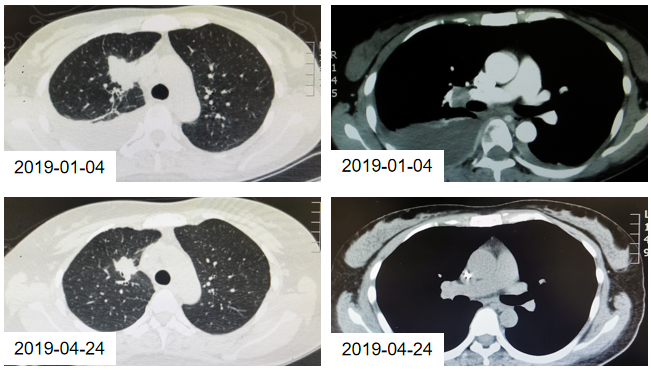

2019年1月14日至2019年3月25日,患者接受4周期的培美曲塞+卡铂(AP)联合贝伐珠单抗治疗,具体方案为:培美曲塞 800mg 静滴 d1 + 卡铂 600mg 静滴 d1 + 贝伐珠单抗 400mg 静滴 d1, q3w;并辅以双膦酸盐类药物(因卡磷酸二钠)抑制骨转移。4周期治疗后影像学疗效评估为部分缓解(PR)。

图1. AP+贝伐珠单抗治疗4周期的CT检查结果

2019年4月19日至2019年10月31日,患者接受10周期的培美曲塞联合贝伐珠单抗维持治疗,具体方案为:培美曲塞 800mg 静滴 d1 + 贝伐珠单抗400mg 静滴 d1,q3w。

图2. AP+贝伐珠单抗治疗维持治疗10周期的CT检查结果